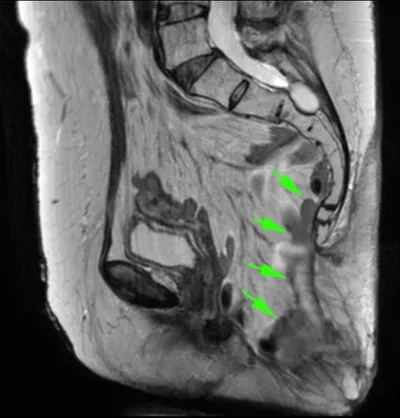

Рецидив атипичной спинальной менингиомы (первые снимки -2,5 года назад, после операции), за последний месяц - ухудшение состояния в виде нижнего парапареза и болей в спине. опухоль диффузная и муфтооб

так полечили рак прямой кишки, что вследствие недостаточности тазового дна газ теперь в кишках бурлит под кошей ягодиц. Первый раз вижу выпадение петель тонкой кишки! Коллеги по началу растерялись,

Метастаз рака почки у пациента 55 лет... 🦞😱